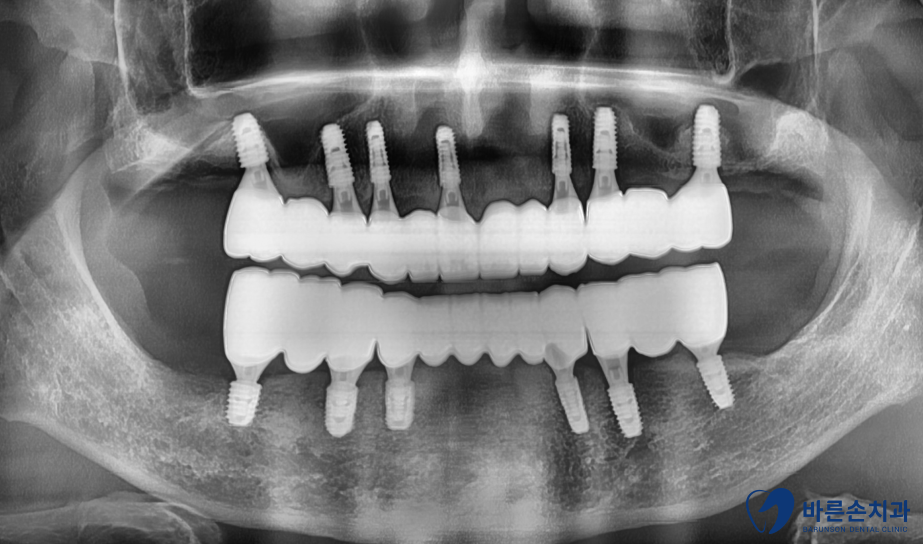

초진 엑스레이

엑스레이 사진으로 보니

잇몸뼈 (빨간 선)가 푹 꺼져서 치아를 잡아주지 못하고 있습니다.

원인은 전부 치석으로 인한 치주병 때문입니다.

최대한 치아를 살리고 싶지만 안타깝게도 전부 살릴 수 없고 발치해야 하네요..

전악 발치, 임플란트 계획을 세우게 되었습니다.

임플란트를 하기 전 CT 사진을 촬영하고 더 자세한 뼈 상태를 봤습니다.

임플란트를 심기 위해서는 최소 8~10mm 정도의 뼈가 있어야 하는데

치주병으로 인해 뼈가 종잇장처럼 얇게 있습니다.

뼈 위에 있는 비어있는 공간 상악동을 활용해서

뼈이식을 하고 임플란트 식립하기로 합니다.

임플란트를 총 13개 식립하고

뼈와 임플란트가 단단하게 붙을 동안 2~3개월 정도 기다려야 합니다.